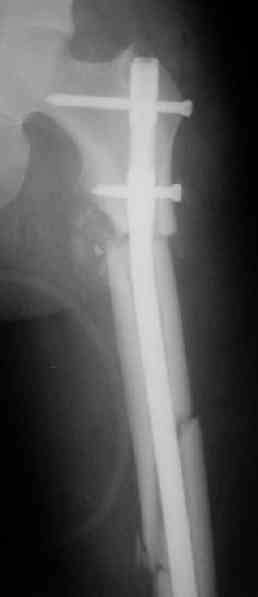

СМ> Если имеются под рукой Р-снимки, продемонстрируйте, плиз.

Вот несколько. С тисками и трубой на днях сделаем.

Саша, последний штифт, пожалуй, перегнули?

> Саша, последний штифт, пожалуй перегнули?

Там заход сделан как для прямого штифта, не через вертел.

И правда, не через вертел. Тогда зачем гнули?